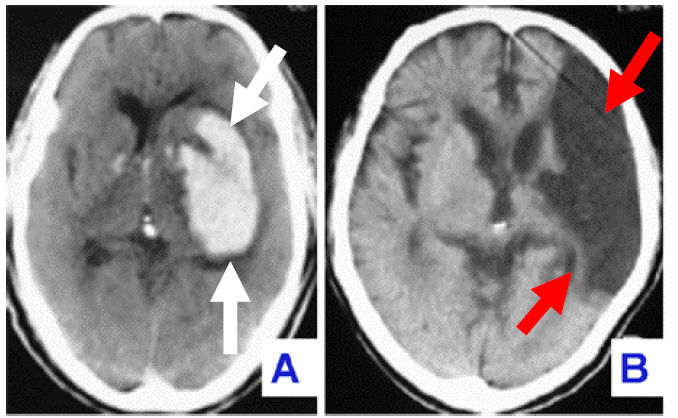

A:CTで撮影した脳内出血の画像白矢印で示した白くなっているところが出血

B:CTで撮影した脳梗塞の画像赤矢印で示した黒くなっているところが梗塞